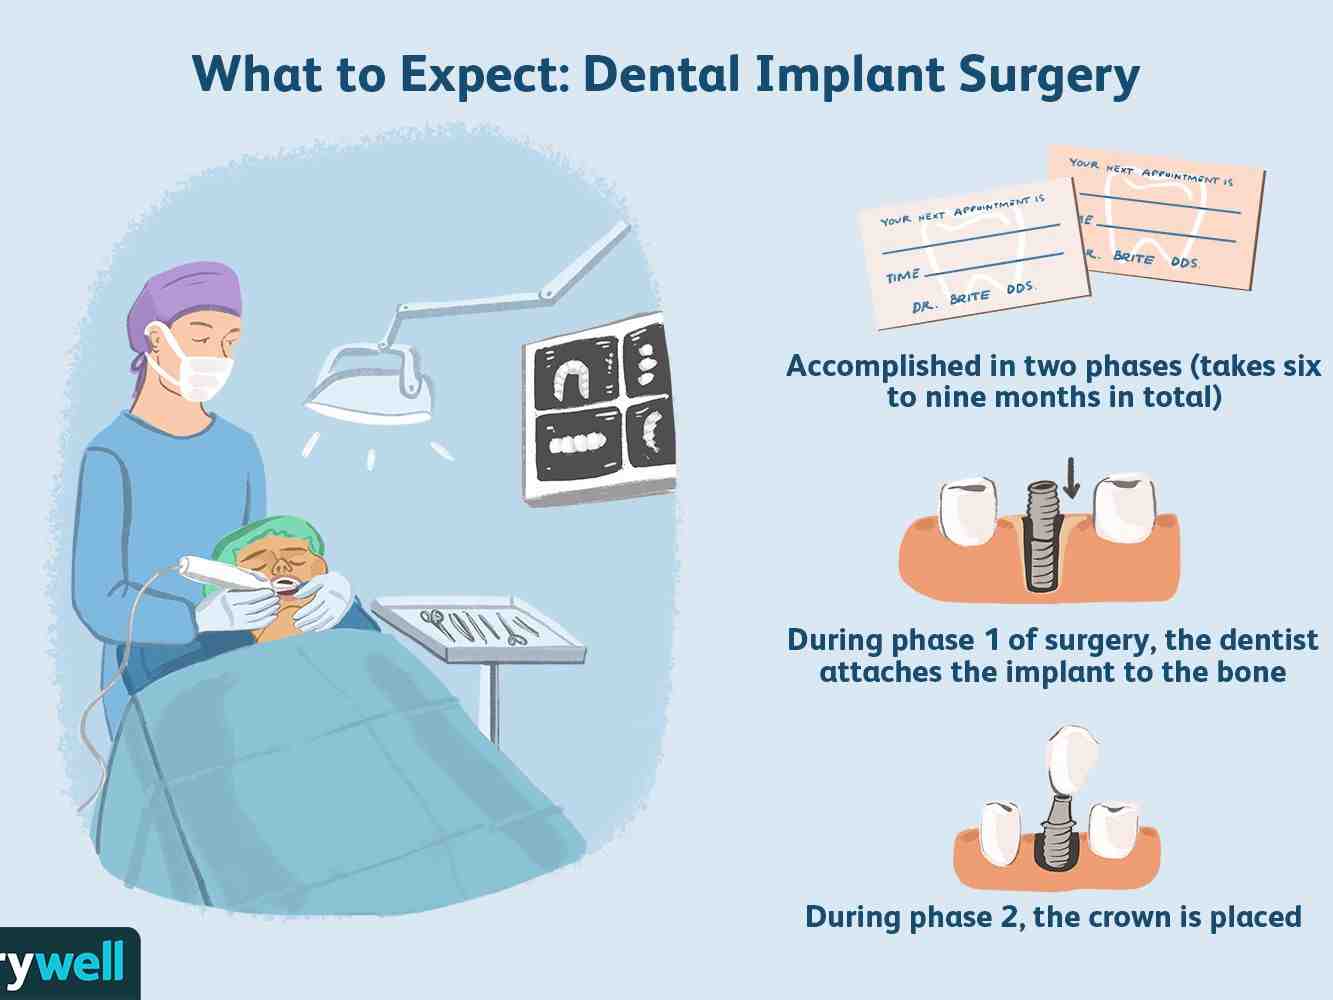

What are the stages of a dental implant?

The dental implant placement process involves several steps, including:

- Removal of a damaged tooth.

- Preparation of the jaws (grafting), if necessary.

- Dental implant placement.

- Bone growth and healing.

- Substrate placement.

- Placing artificial teeth.